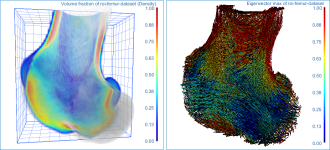

This section describes the different settings that can be applied to the vector field-based anisotropy map that was computed in this tutorial.

Below are some examples of vector field-based anisotropy maps shown from different aspects. The top row includes visualizations of anisotropy magnitude, while the bottom row shows vector fields colored by orientation. The pair of images on the right show maps that are clipped.

The 3D vector field-based anisotropy map appears in the 3D view at the default settings, with the vectors corresponding to the highest surface anisotropy colored yellow and those corresponding to the lowest, or isotropy, colored blue.

NOTE The Jet LUT is often a good color scheme choice. In this LUT, vectors corresponding to the highest surface anisotropy are colored red, while those corresponding to the lowest, or are isotropic, are colored blue.

- Check the Use direction as color option.

Checking this option will re-code the vector map in accordance with the orientation of the vectors — red for the X axis, green for the Y axis, and blue for the Z axis.